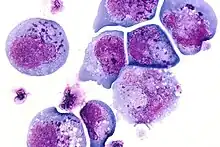

Fritz Heinrich Jakob Lewy, a German-American neurologist, first identified and described inclusions in the brain cells of patients with Parkinson's disease and published his findings in the Lewandowsky's Handbook of Neurology in 1912.[2] I-cells also called inclusion cells are abnormal fibroblasts having a large number of dark inclusions in the cytoplasm of the cell (mainly in the central area). They are metabolically inactive structures of a cell and are not enclosed by a membrane.[3] The inclusions are of various fats, proteins, carbohydrates, pigments, excretory products, crystals,[4] and other insolubles. They are found in the cytoplasm of a cell in both prokaryotes and eukaryotes.[5] They are seen in Mucolipidosis II,[6] and Mucolipidosis III, also called inclusion-cell or I-cell disease where lysosomal enzyme transport and storage is affected.[7]